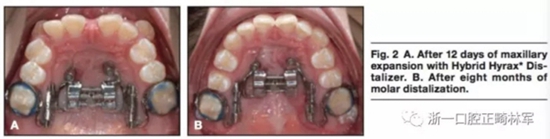

局麻下將兩枚2mm*9mm的微種植體植入鄰近腭中縫處。在上頜第一前磨牙處使用不銹鋼絲。使用聚乙烯硅氧烷上頜取模以制造Hybrid。局麻下翻開粘骨膜瓣使用4枚皮質(zhì)釘以在下頜前牙放置鈦板。通過轉(zhuǎn)動矢狀向的螺釘90°4次以激活擴(kuò)弓器,0.2mm每次,0.8mm每天。鈦板使用皮筋在兩側(cè)直接加400g前牽力。12天后,上頜前磨牙間橫向?qū)挾仍黾拥?mm。(圖2,A)矢狀螺釘在磨牙遠(yuǎn)移階段固定,每周激活雙側(cè)遠(yuǎn)移螺釘(0.2mm每周)。8個月后磨牙遠(yuǎn)移4mm(圖2B),該階段繼續(xù)掛皮筋。